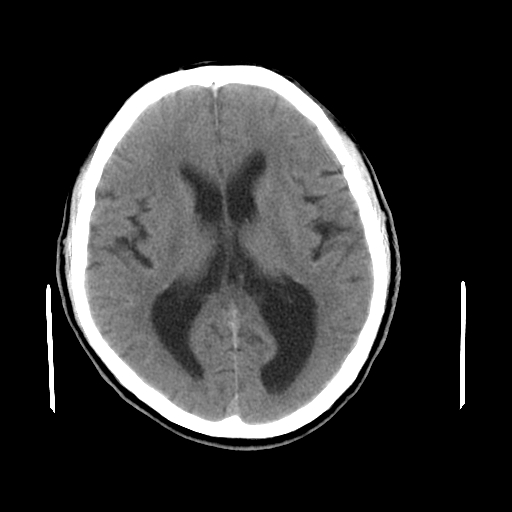

男,64岁,左侧肢体活动障碍两天。

好像有轻度积水改变。

侧脑室有点怪怪的

拟:轻度脑积水,治疗后复查。(如果你说的时间准确的话,左侧肢体活动不便,不会是脑卒中所引起,是不是高血压引起的血管痉挛呢?请结合临床)。

考虑 脑萎缩,脑积水待排

未见异常,侧脑室后角应该是正常变异

目前看是双侧侧脑室有轻度扩张,建议结合临床治疗后复查,

除侧脑室轻度扩大外无其他异常发现

考虑轻度脑积水

轻度脑积水